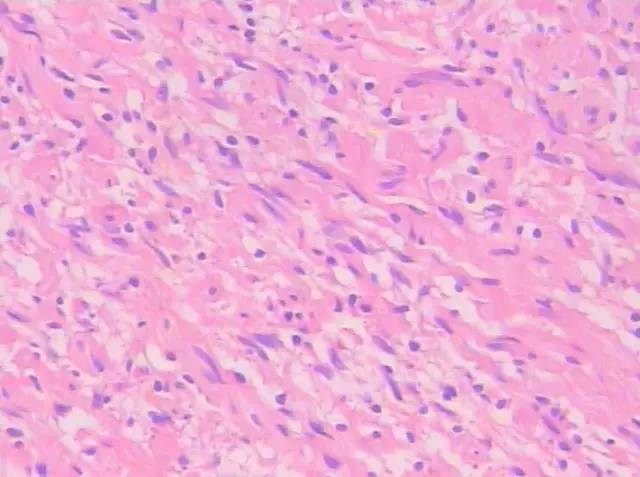

肉眼所见左侧精囊灰黄色包块,大小约4.5 cm×3.2 cm×2.6 cm,切面灰黄实性,质嫩。光镜下示瘤细胞核小,卵圆,无明显的细胞突起,为梭形细胞肿瘤(图4、5);免疫组化:S-100( ),EMA(-),CK(-),VIM( ),CD34(部分 ),CD117(-)(图6)。

图4、5 镜下示瘤细胞核小,卵圆,无明显的细胞突起(图4X100,图5X200,HE)

神经鞘膜来源肿瘤内常见两种不同密度的实体成分即细胞致密区(Antoni A 区)和细胞稀疏区( Antoni B 区)[1]。神经鞘膜来源肿瘤的密度与Antoni A 区和Antoni B 区的比例、分布和排列有关;富细胞区为主或者只含有富细胞区, 病变密度较高,强化较明显; 细胞稀疏区为主或者只含有细胞稀疏区时, 肿瘤密度很低,强化不明显。本例肿块在光镜下可见细胞稀少及疏松网状背景,考虑肿瘤以细胞稀疏区为主;超声示肿块内部为低回声,后方回声无变化,彩色多普勒显示肿块内部可见少许点状血流信号;CT示肿瘤密度较低,几无强化;其影像表现与病理相符。